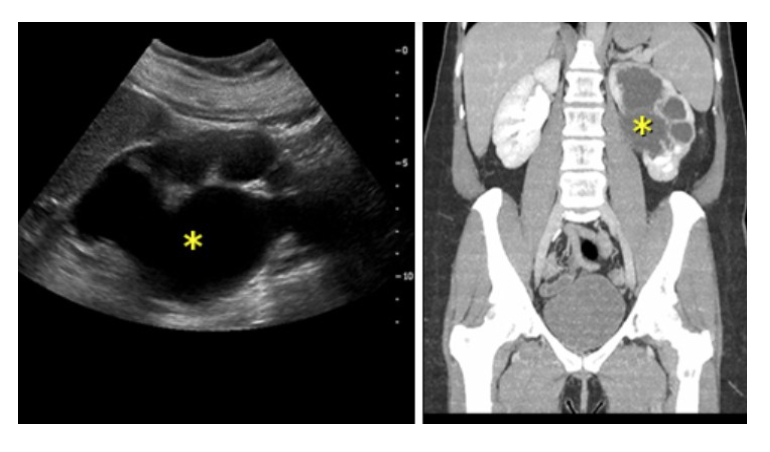

Describe the classic presentation of pyelonephritis

What is the diagnosis

L sided pyelonephritis